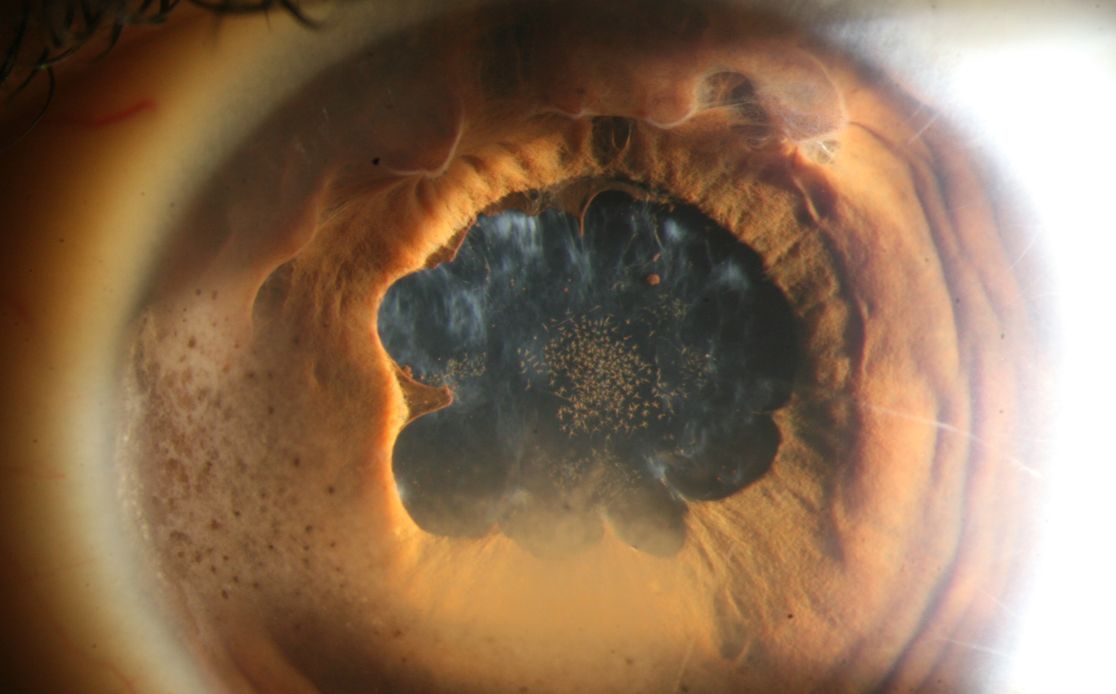

Krankes Auge

Uveitis-Kurs

Der Uveitis Kurs soll in Weiterbildung befindenden Personal sowie augenärztlichen Fachpersonal die Möglichkeit bieten, ihr Wissen über intraokulare Entzündungen zu vertiefen.